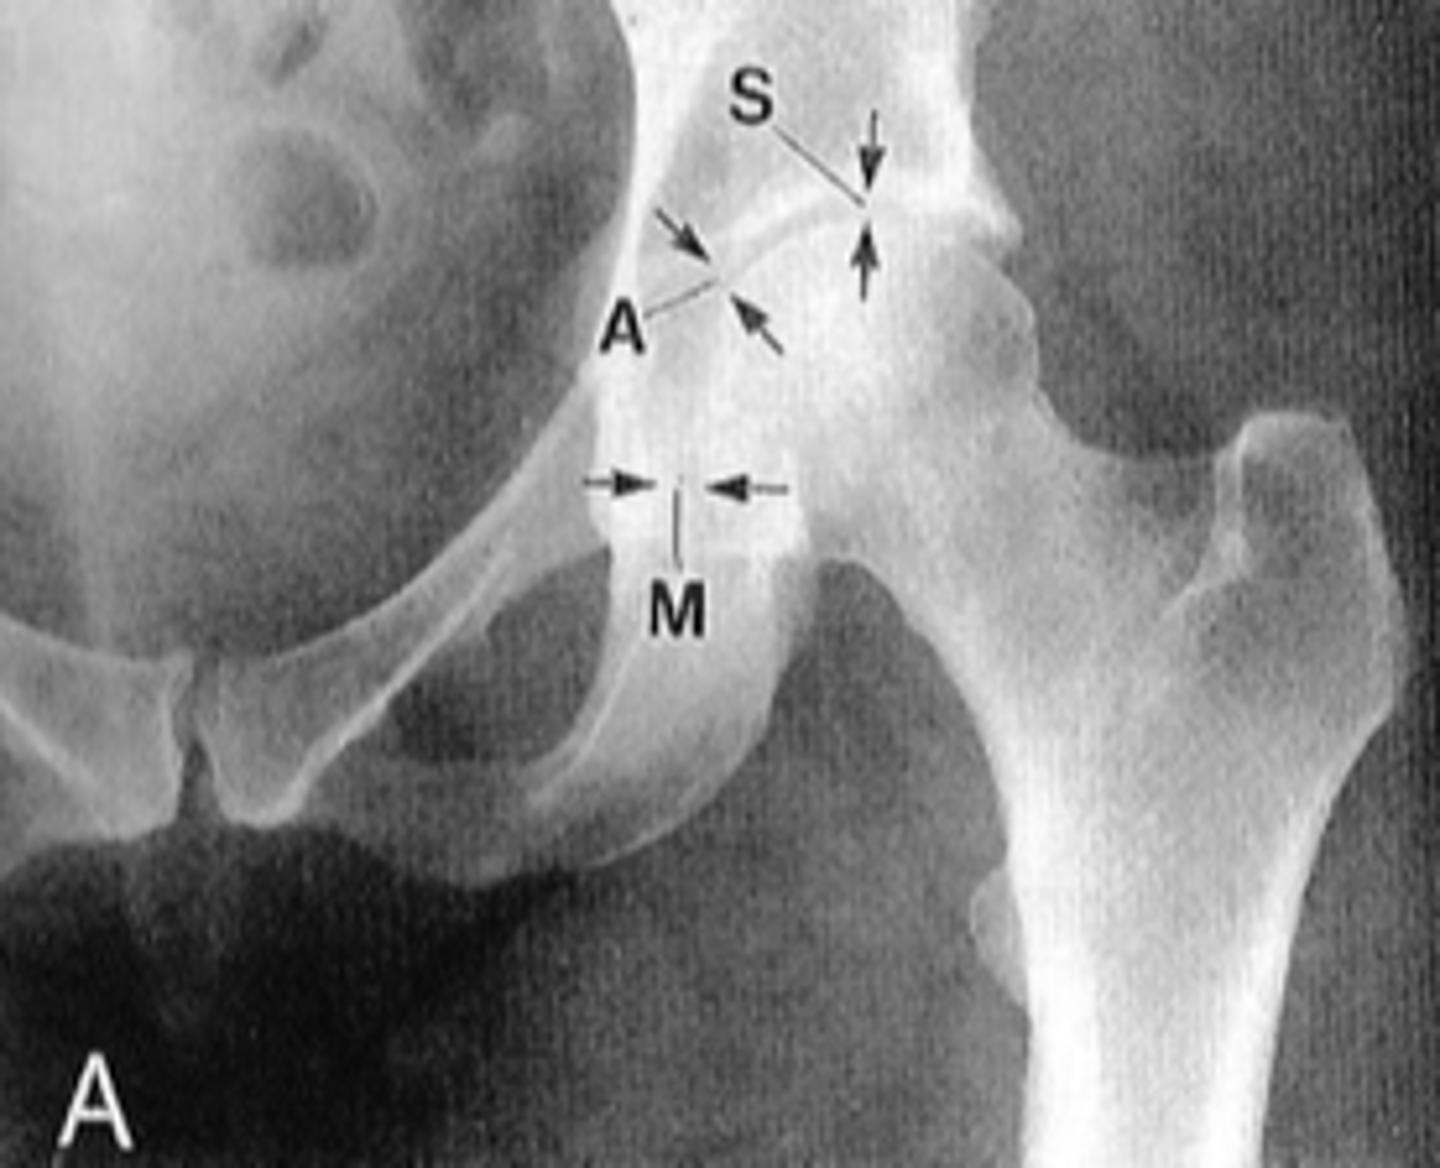

Shenton's line

ID measurement

- AP hip

- AP pelvis

What views are used to see Shenton's line?

<p>What views are used to see Shenton's line?</p>

- Smooth arc along femoral neck

- Obturator foramen

Shenton's line landmarks

<p>Shenton's line landmarks</p>

Continuous and smooth

Shenton's line normal measurements

<p>Shenton's line normal measurements</p>

- Hip dislocation

- Femoral neck fracture

- Slipped epiphysis

Clinical significance of Shenton's line

<p>Clinical significance of Shenton's line</p>

Femoral angle

What views are used to measure the femoral angle?

<p>What views are used to measure the femoral angle?</p>

- Mid-axis of femoral shaft

- Mid-axis of femoral neck

- Intervening angle

Femoral angle landmarks

<p>Femoral angle landmarks</p>

120-130˚

Normal femoral angle measurement

<p>Normal femoral angle measurement</p>

Coxa vara

Femoral angle <120˚

<p>Femoral angle &lt;120˚</p>

Coxa valga

Femoral angle >130˚

<p>Femoral angle &gt;130˚</p>

Skinner's line

What views are used to see Skinner's line?

<p>What views are used to see Skinner's line?</p>

- Right angle tangent to tip of greater trochanter

Skinner's line landmarks

<p>Skinner's line landmarks</p>

Fovea capitis should lie above or at level of trochanteric line

Skinner's line normal measurement

<p>Skinner's line normal measurement</p>

Fracture or other causes of coxa vara

Clinical significance of Skinner's line

<p>Clinical significance of Skinner's line</p>